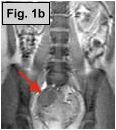

Fig. 1a-c: MRI of the L-spine (sagittal T2 weighted, coronal scout, and coronal MR Myelogram, respectively) demonstrates an incidental 4-5 cm cystic-appearing mass in the right pelvis on limited views of the pelvis. Fig. 2: a helical CT image of the pelvis, revealing a 4x5 cm low-density mass in the right hemipelvis to the right of the uterus. Fig. 3: Pelvic ultrasound shows a moderately enlarged right adnexa measuring 5 cm with low-level echoes.

IMAGING FINDINGS:  Fig. 1a-c show MRI images of the L-spine (sagittal T2 weighted, coronal scout, and coronal MR Myelogram, respectively).  They demonstrate mild scattered disc bulges and an incidental 4-5 cm cystic-appearing mass in the right pelvis on limited views of the pelvis. Incidentally, the MR Myelogram (Fig. 1c) also nicely shows the thecal sac and renal collecting systems.  Fig. 2 shows a helical CT image of the pelvis, revealing a 4x5 cm low-density mass in the right hemipelvis to the right of the uterus with CT density of about 20 Hounsfield units on pre- and post-contrast images.  A repeat transabdominal and endovaginal pelvic ultrasound with Doppler performed at AIC (Fig. 3) showed a moderately enlarged right adnexa measuring 5 cm with low-level echoes.